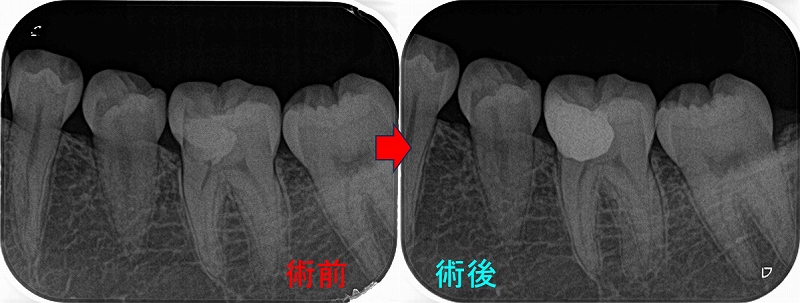

今年になり患者さんが詰め物が外れたとのことで来院

2026 EEdental FUD (6).jpg

10年経過して、そこまで悪い感じはありません。

患者さんにも「先生にそんなに持たないかもしれないよと言われていましたが10年持っています。意外と持つものですね!」と言われましたが、

ホント最初の延長ブリッジの方がかなり良い条件でしたが、折れてしまった。

パフォレーション+分割抜歯、移植した歯という条件の悪いケースで10年経過している。。。

たぶん、私がそんなに持たないかも!?と言った事でかばって咬むようにしているのが

今の状況を作っていると思いますが、ホント術者がどんなに頑張っても咬む力(歯ぎしり含め)で歯は必ず悪くなってきてしまいます。

こういうケースを見ると、患者さんの協力なしで歯を長く持たせることは難しいと感じます。

今回のケースは詰め物のやり替えだけ行えば、またしばらく使うことは可能でしょうd(^。^)